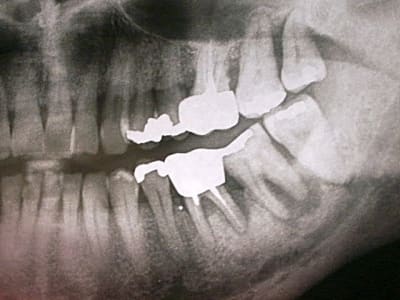

patient, 65 ans, ami proche de la famille, pére d'un très bon ami d'enfance.

douleurs récurrentes au maxillaire droit à la mastication.

sensations de dents + ou - mobiles au max D et mand G.

Habitudes: visite annuelle chez son CD. a effectué les soins et prothèses conseillés. Pas de gros travaux entrepris depuis 20 ans. utilise un hydropulseur en plus du brossage (mais ne sait surement pas que son efficacité sur la PD est nulle).

Dernière visite chez son CD: 3 mois... pour la même raison. RAS tout va bien (???) + un ATB et roule ma poule... (???).

n'a plus trop confiance dans son CD...

motivation: ok. prêt à faire des kms pour venir me voir. prêt à faire de gros rdv (2H).

Je l'ai envoyé faire une pano en attendant de le voir en consultation. Bigre!!!!

premières impressions?

Manifestement alvéolyse horizontale généralisée, 25% de perte d'attache à 65 ans : je penche pour une parodontite chronique de l'adulte.

Suffisant s'il n'y avaient pas ces facteurs aggravants que sont les pulpectomies déficientes, couronnes débordantes et mal ajustées.

Je soupçonne aussi un trauma occlusal.

Mais 47 est HS.

Une fois extraite que faire?

Implant?

Bridge?

ODF pour mésialiser 48? Je doute que ce soit possible.

En l'état actuel de mes compétences, connaissances c'est sûr que l'implant l'emporte.